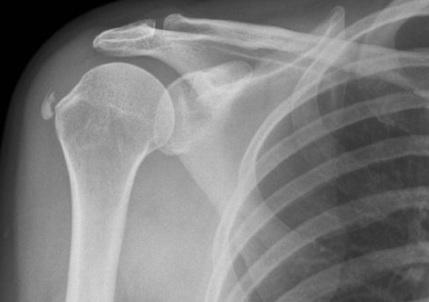

Shoulder is one of the largest and most complex joints in the body and is made up of three bones: the clavicle (collarbone), the scapula (shoulder blade), and the humerus (upper arm bone) as well as associated muscles, ligaments and tendons. It is also the joint which provides the widest range of motion of any part of the body. Hence it is predisposed to injuries, dislocations and general wear and tear.

Shoulder joint osteoarthritis

Osteoarthritis is a degenerative condition of the joints seen in the elderly people and is characterised by loss